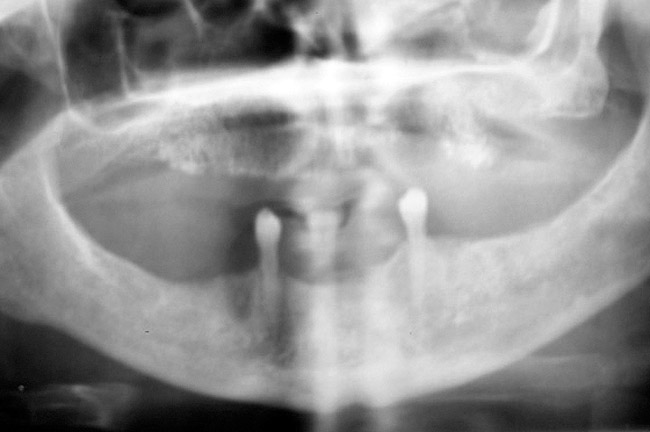

Figure 4  Radiograph of oral bisphosphonate user.

Figure 4

Under the sextant approach, one quadrant is treated and the patient is left to heal for 2 months before proceeding to any additional quadrants. While the patient heals, a 10-day course of antibiotics and 2 months of twice-daily chlorhexidine rinsing may be prescribed. Figure 4 shows a patient who was taking oral bisphosphonates for 3 years and was treated with the sextant approach. As seen in the radiograph, the patient has one molar in the lower right quadrant. This tooth was extracted and the patient was given 2 months to heal (Figure 5 and Figure 6). The patient was placed on antibiotics and chlorhexidine rinse. After 2 months, no signs of BRONJ were observed, and the anterior teeth were scheduled for extraction. They were extracted as atraumatically as possible, and the site was sutured (Figure 7 and Figure 8).The patient then was given another 2 months to heal, following the previous protocol. After 2 months of healing, no BRONJ was observed (Figure 9).